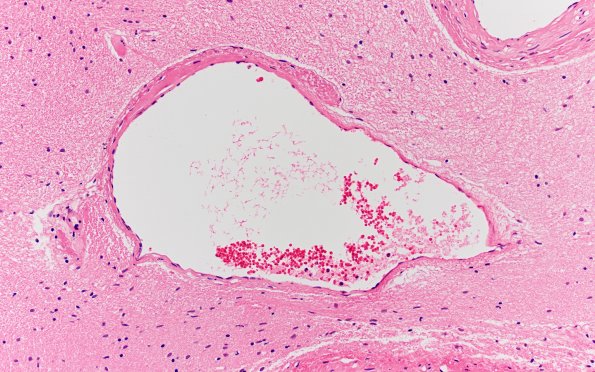

34B6 AVM, hybrid vessels (Case 34) H&E 20x

A particularly nice example of a hybrid vessel. (H&E)